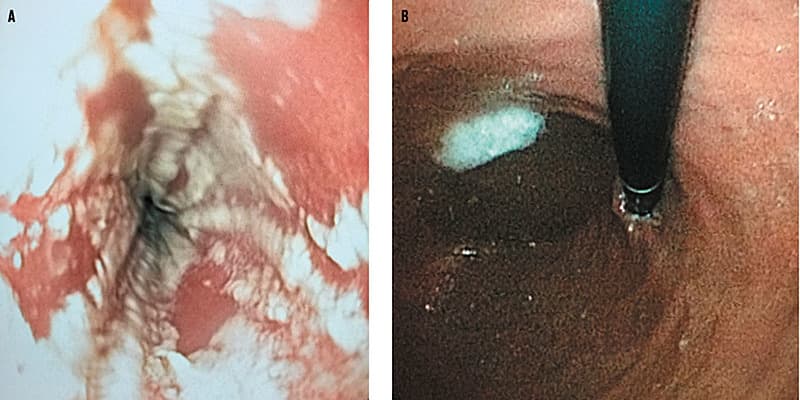

En 18-årig kvinde blev henvist akut til en øre-næse-hals-afdelingen obs. synkestop samt synkesmerter i halsen og retrosternalt, men hun kunne stadig drikke tynde væsker i små mængder. Ved øsofagoskopi og gastroskopi noteredes hvidlige belægninger på slimhinderne (A) , og i de mikrobiologiske prøver påvistes Candida albicans. Derimod sås der ingen større slimhindeforandringer i ventriklen (B).

Der blev påbegyndt fluconazolbehandling, som havde god effekt, og patienten var i sin habitualtilstand ved den afsluttende kontrol 14 dage efter udskrivelsen.